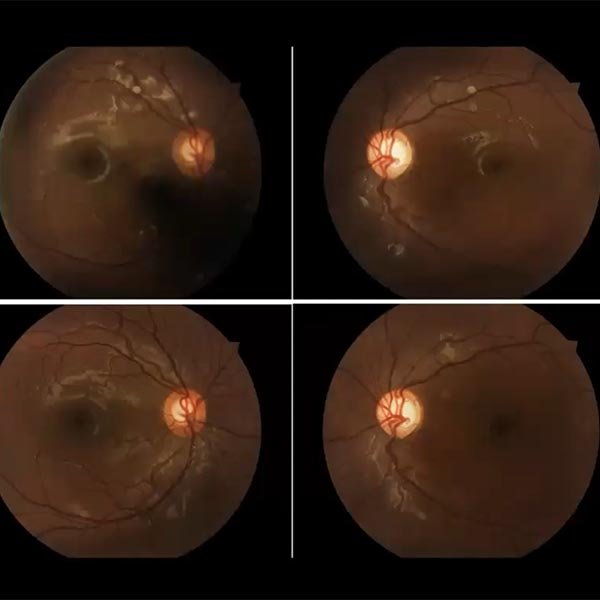

Treat and extend?

Maria Rosario Alcorta